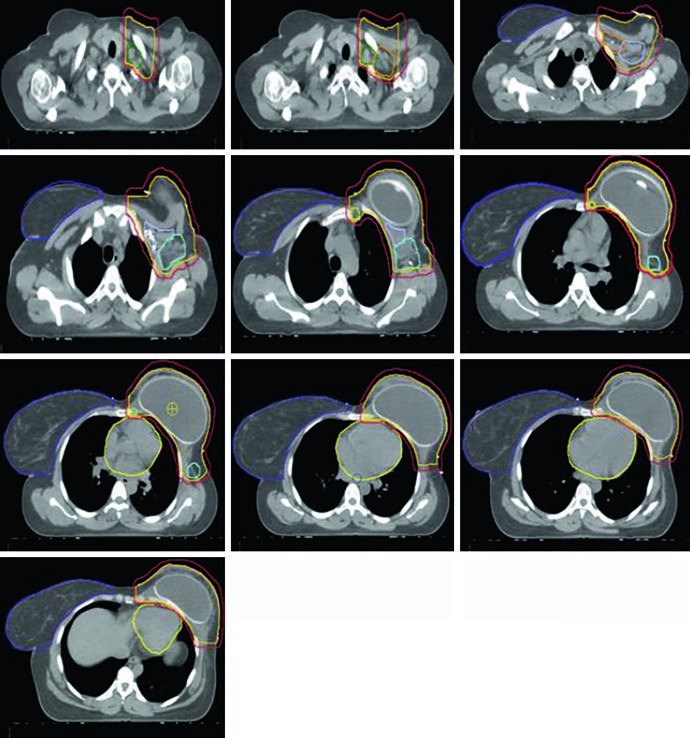

Reconstructed (Tissue Expander) Left Chest Wall

When the patient has tissue expander reconstruction, the planning geometry changes significantly. The expander protrudes the chest wall anteriorly, altering target depths and the spatial relationship with OARs. On the left side, the heart assumes a relatively more anterior position, requiring careful optimization. Figure 12.4 clearly shows the cardiac contour (yellow) in relation to the PTV in the sagittal view — this proximity explains the laterality-specific dosimetric limits.

Figure 12.5 shows axial slices for the reconstructed left chest wall. Note how the PTV encompasses the expander bilaterally and how nodal stations maintain their standard contours despite the anatomical alteration. The prosthesis itself is included in the CTV — the IMRT/VMAT criteria specify that the $D_{95\%}$ inside the implant PTV should not exceed 120% of the prescription, an essential limit to avoid damage to the prosthetic material and capsular complications. In practice, hot spots above 120% over silicone or saline expanders can cause accelerated encapsulation and complicate subsequent reconstructive surgeries.